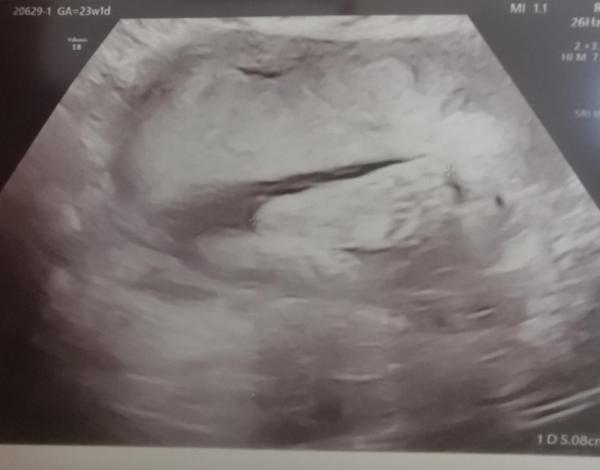

Hallo ihr Lieben, ich komme gerade von meinem Vorsorgetermin bei meiner Gynäkologin. Nachdem ich vor nicht ganz zwei Wochen bei der Feindiagnostik schön verunsichert wurde zwecks Diabetes und zu viel Fruchtwasser, hatte ich heute die Wiederholung vom großen Zuckertest. Das Ergebnis bekomme ich morgen Vormittag telefonisch mitgeteilt, ich hoffe es ist immernoch unauffällig und der Schwangerschaftsdiabetes bleibt weiterhin ausgeschlossen. 🍀 Meine Ärztin nahm mir aber auch ein Stück weit die Unsicherheit, da wirklich alle Werte der Maus zwischen der 95. und 98. Perzentile liegen. Das ist untypisch für Diabetes, da dort hauptsächlich der Bauchumfang im Vergleich zu sonst der Woche entsprechenden Werten auffällig ist. Zum Fruchtwasser meinte sie, dass der Arzt bei der Feindiagnostik das falsch gemessen hat. Ich habe NICHT zu viel Fruchtwasser. Bei der Feindiagnostik wurde nur ein Durchmesser aus der Fruchtblase gemessen, um so eine Diagnose zu stellen benötigt es aber 4 (damit kommt man dann auf den Fruchtwasser-Index) aus allen Quadranten der Gebärmutter. Und so stehe ich zwar an der oberen Grenze, aber noch im Normbereich. Ich bin erleichtert. Die Maus hat sich von zuletzt BEL in SL gedreht, das habe ich aber auch schon gemerkt, da ihre Füße nicht mehr gegen meine Blase getreten haben, sondern stattdessen schön weit oben fast am Rippenbogen. 😁🫣 Sie hat in der kurzen Zeit fast 200g zugenommen und ist 4cm gewachsen, sodass sie jetzt schon 810g auf 32cm hat. Ihr Kopfumfang liegt bei 23cm. Meine Ärztin hat heute sogar kurz auf 4D umgeschwenkt, aber - wie auch sonst - hatte die Maus ihre Hände vorm Gesicht und ließ sich nicht überzeugen, das Gesicht wenigstens mal kurz vollständig zu zeigen. Aber nichtsdestotrotz war das ein unfassbar schöner Moment, bei den Feindiagnostiken waren es "nur" Standbilder, heute dann live in Bewegung. 😍🩷 Ich soll jetzt nicht mehr alle 4 sondern alle 3 Wochen zur Vorsorge und da wird auch jedesmal nochmal nach dem Fruchtwasser und der Größe geschaut. Meine Ärztin meinte auch, wenn das tendenziell so weiter geht mit dem Wachstum, dann wird es wohl auf ein über 4kg Baby hinaus laufen und man müsste gegen Ende schauen, ob vielleicht eingeleitet wird. Das wollte ich aber eigentlich um jeden Preis vermeiden. 🙁 Mal sehen. Ansonsten habe ich ein Teilbeschäftigungsverbot ausgestellt bekommen, denn ich soll auf noch mehr Ruhe achten und mein Blutdruck muss ab jetzt eingestellt und dadurch häufiger gemessen werden. Eventuell wird daraus aufgrund der Symphyse ein komplettes Beschäftigungsverbot, dazu soll ich mich gerne jederzeit melden, das wäre wohl kein Problem. Aber dazu will ich erstmal abwarten, ob die Reduzierung alleine schon was bringt. Es gibt wohl noch einen richtigen Symphysengurt (ich hatte bisher einen anderen, der den Bauch stützt), der mich in meiner Bewegung aber soweit einschränken würde, dass ich überwiegend nur liegen könnte bzw. zumindest das Laufen nicht mehr richtig möglich wäre. Das will ich erstmal umgehen, solange möglich.  An die von euch, die ebenfalls ein Beschäftigungsverbot erhalten haben - musstet ihr auch 50€ für die Ausstellung bezahlen? Wie geht es euch so mit der fortgeschrittenen Schwangerschaft? Wie sind eure Beschwerden, wann habt ihr wieder Vorsorge, wie läuft der Alltag mit immer größer werdendem Bauch? Liebe Grüße Susuba, 23+1

Bild zu Update Verlauf Schwangerschaft - Forum für Mai - Mamis